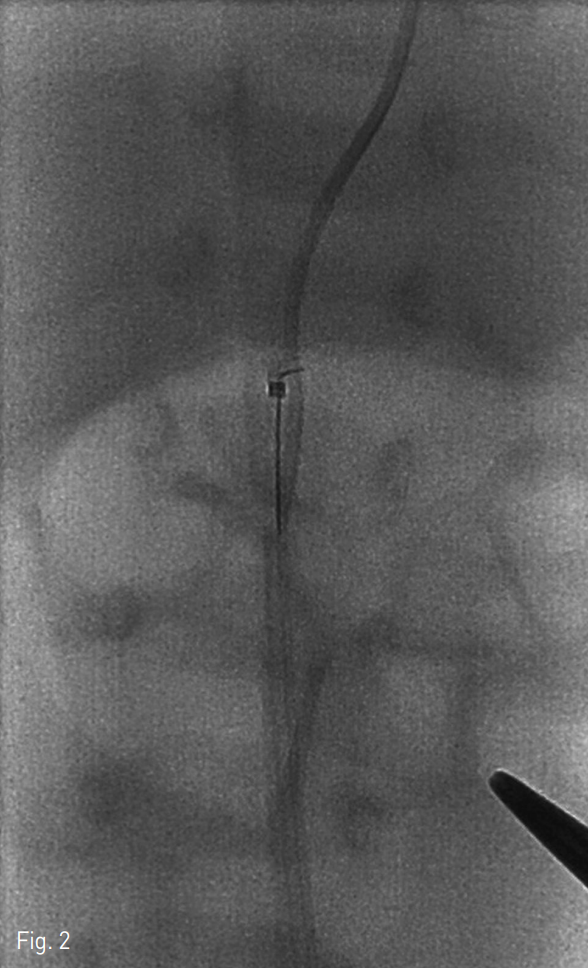

단순 X-ray촬영상 절단된 제대정맥관이 제대정맥과 우심방 사이에 관찰되었다(Fig. 1).

Fig. 1A

Anteroposterior (A) and lateral (B) plain x-rays showing the broken UVC between the umbilical vein and right atrium